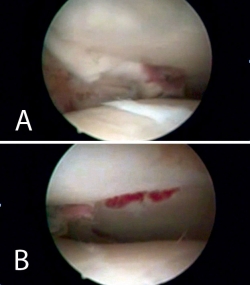

Nos colocamos sentados frente al miembro lesionado, elevando la mesa quirúrgica con la pantalla de la torre de artroscopia frente a nosotros. Tras realizar los portales de artroscopia, procedemos a un lavado exhaustivo de la articulación dejando introducir el suero de la bolsa de artroscopia (no utilizamos bomba de presión) hasta que dejen de salir restos de hematoma por el aspirador de artroscopia. A continuación, introducimos el sinoviotomo y resecamos el hemartros fracturario hasta que identifiquemos los fragmentos del foco de fractura (Figuras 4 y 5).

Figura 5. Lavado exhaustivo. Desbridamiento del hemartros y limpieza articular.

Figura 8. Percusión del fragmento con el impactor, control radioscópico de la posición del impactor e imagen artroscópica del escalón articular antes de la reducción.

Figura 9. Imagen artroscópica de la reducción del fragmento hundido y del trazo articular.